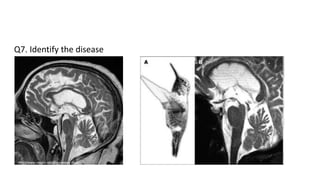

Q3

A 65 year old man presents to the medicine OPD with complaints of

dizziness, difficulty in speaking, difficulty swallowing food at dinnertime and

a ‘wobbly gait’ since the past 1 month. He also gives a history of weakness

in his arms and legs as the day progresses which improves with some

activity. He has 50 pack year smoking history. On examination his vitals are

stable. On neurological examination there is horizontal nystagmus

bilaterally, he has an ataxic gait and demonstrates past pointing on a finger

nose test. Muscle bulk, tone and power are normal in all 4 limbs with

normal sensory exam. His CBC reveals mild anemia, leukopenia and leuko-

erythroblastic blood picture on PS itself.

MRI Brain, CECT chest and Pathology findings from CT guided biopsy are

shown